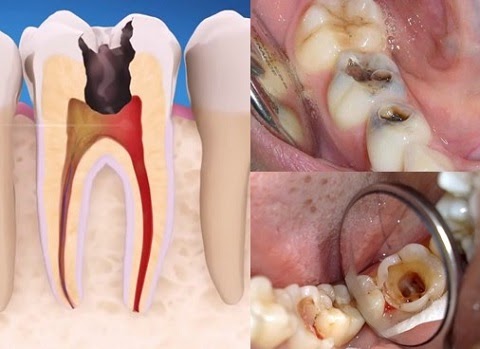

Chữa tủy răng là quá trình loại bỏ phần tủy bị nhiễm trùng hoặc chết ra khỏi răng. Nếu không được chữa trị kịp thời, vi khuẩn có thể lan rộng, gây nhiễm trùng và dẫn đến áp xe – một túi mủ đau đớn hình thành ở gốc răng. Nhiễm trùng răng không chỉ gây đau nhức mà còn có thể ảnh hưởng đến các răng lân cận và xương hàm.

Khi mất tủy, răng trở nên giòn và dễ gãy hơn do thiếu dưỡng chất từ tủy. Điều này đặc biệt nghiêm trọng đối với các răng hàm, những răng chịu lực nhai lớn.

Dấu hiệu khi răng hư tuỷ là: Răng mất tủy thường thay đổi màu sắc, trở nên sậm màu hoặc xám hơn so với các răng khác. Điều này ảnh hưởng đến thẩm mỹ của nụ cười và có thể làm giảm tự tin khi giao tiếp.

Mặc dù tủy đã bị loại bỏ, nhưng nguy cơ nhiễm trùng vẫn tồn tại nếu không được chăm sóc đúng cách. Vi khuẩn có thể xâm nhập vào các kẽ răng hoặc vùng chân răng, gây ra các vấn đề nhiễm trùng tái phát và áp xe.